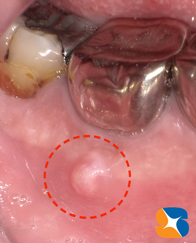

膿みで歯茎が膨らむ 60代の男性。主訴は「同じ所がよく腫れる。他院では[歯磨き不足のため抜歯が必要]と言われた。でも歯磨きは頑張ってやっている。痛くもないので、残したい」でした。

歯茎が膿んでいた所をレントゲンで確認 上記写真の膿んでいた所(=赤点)をレントゲンで確認すると、黒色の濃い影(=赤点)が写っていました。根と根の股間にトラブルが生じていることが判明しました。